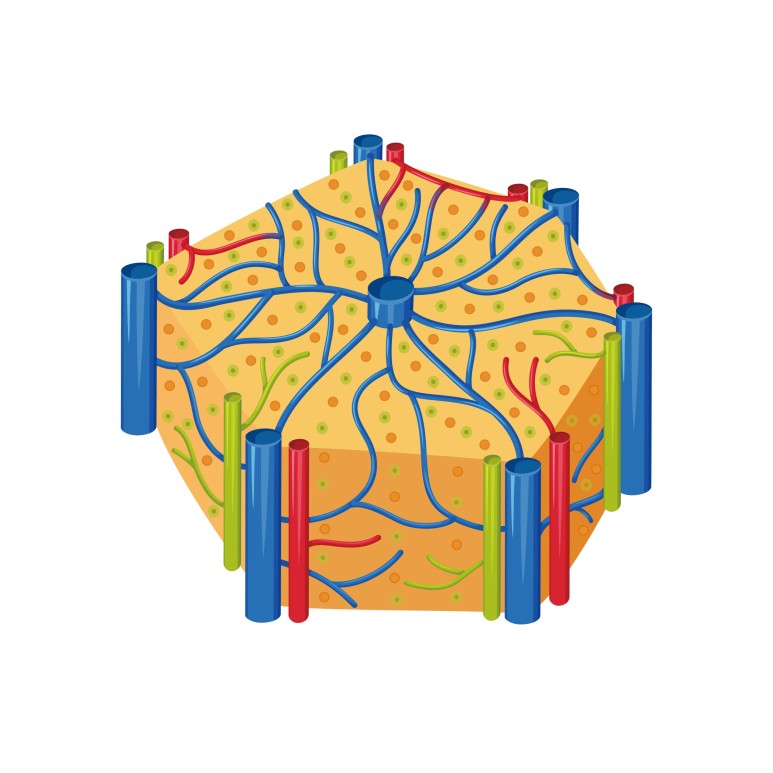

담관이 폐쇄되면 간에도 영향을 미칩니다.

담관주위 담즙유출, 문맥주위염증, 담관확장, 담전형성 등으로 간조직에 변화가 발생합니다.

시간의 흐름에 따라 담즙에 의한 간경화가 발생할 수 있으므로 주의하시기 바랍니다.

담즙성 간경변이 발생할 경우 담관의 압력을 낮추려고 담관의 배액을 수행해도 간경변이 유지되는 비가역적 변화가 발생할 수 있습니다.

이로 인해 담관염이 빈번하게 발생하여 간농양도 발생할 수 있으므로 주의해 주십시오.

담관폐쇄로 인해 담즙이 정체되어 있는 경우 세균증식이 자주 이루어지며 담관염이 발생합니다.담석으로 막혔을 때 흔히 발생하며 담석에 세균이 많이 분포되어 있어 부분적으로 폐쇄되는 경우 사이를 통해 세균이 담관 상부로 유입될 수 있기 때문입니다.

담관폐쇄시 인지질, 담즙액, 담즙산, 콜레스테롤 분비가 감소하는 모습을 보이며 간의 담즙분비 양상에도 변화가 생깁니다.